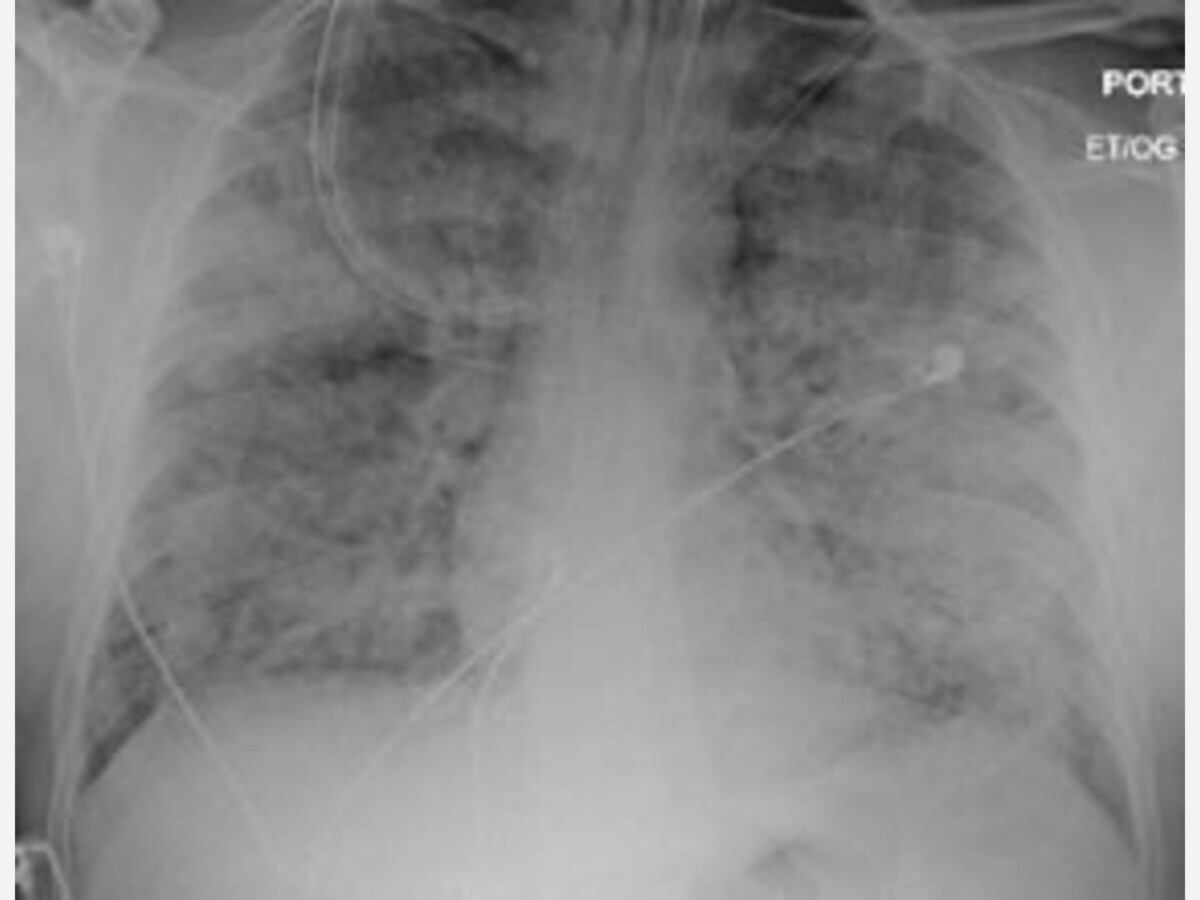

"First and foremost, patients should know that the term “white lung syndrome” is not a medical term. Some people have started to use this term to describe pneumonia such as those cases which have been described recently in Ohio. The term “white lung” comes from the visual description of what we see on x-rays in cases of pneumonia. The lung appears white in the affected areas on x-ray, instead of black. This description would apply to any case of pneumonia, and is no cause for alarm," said Kenkare.